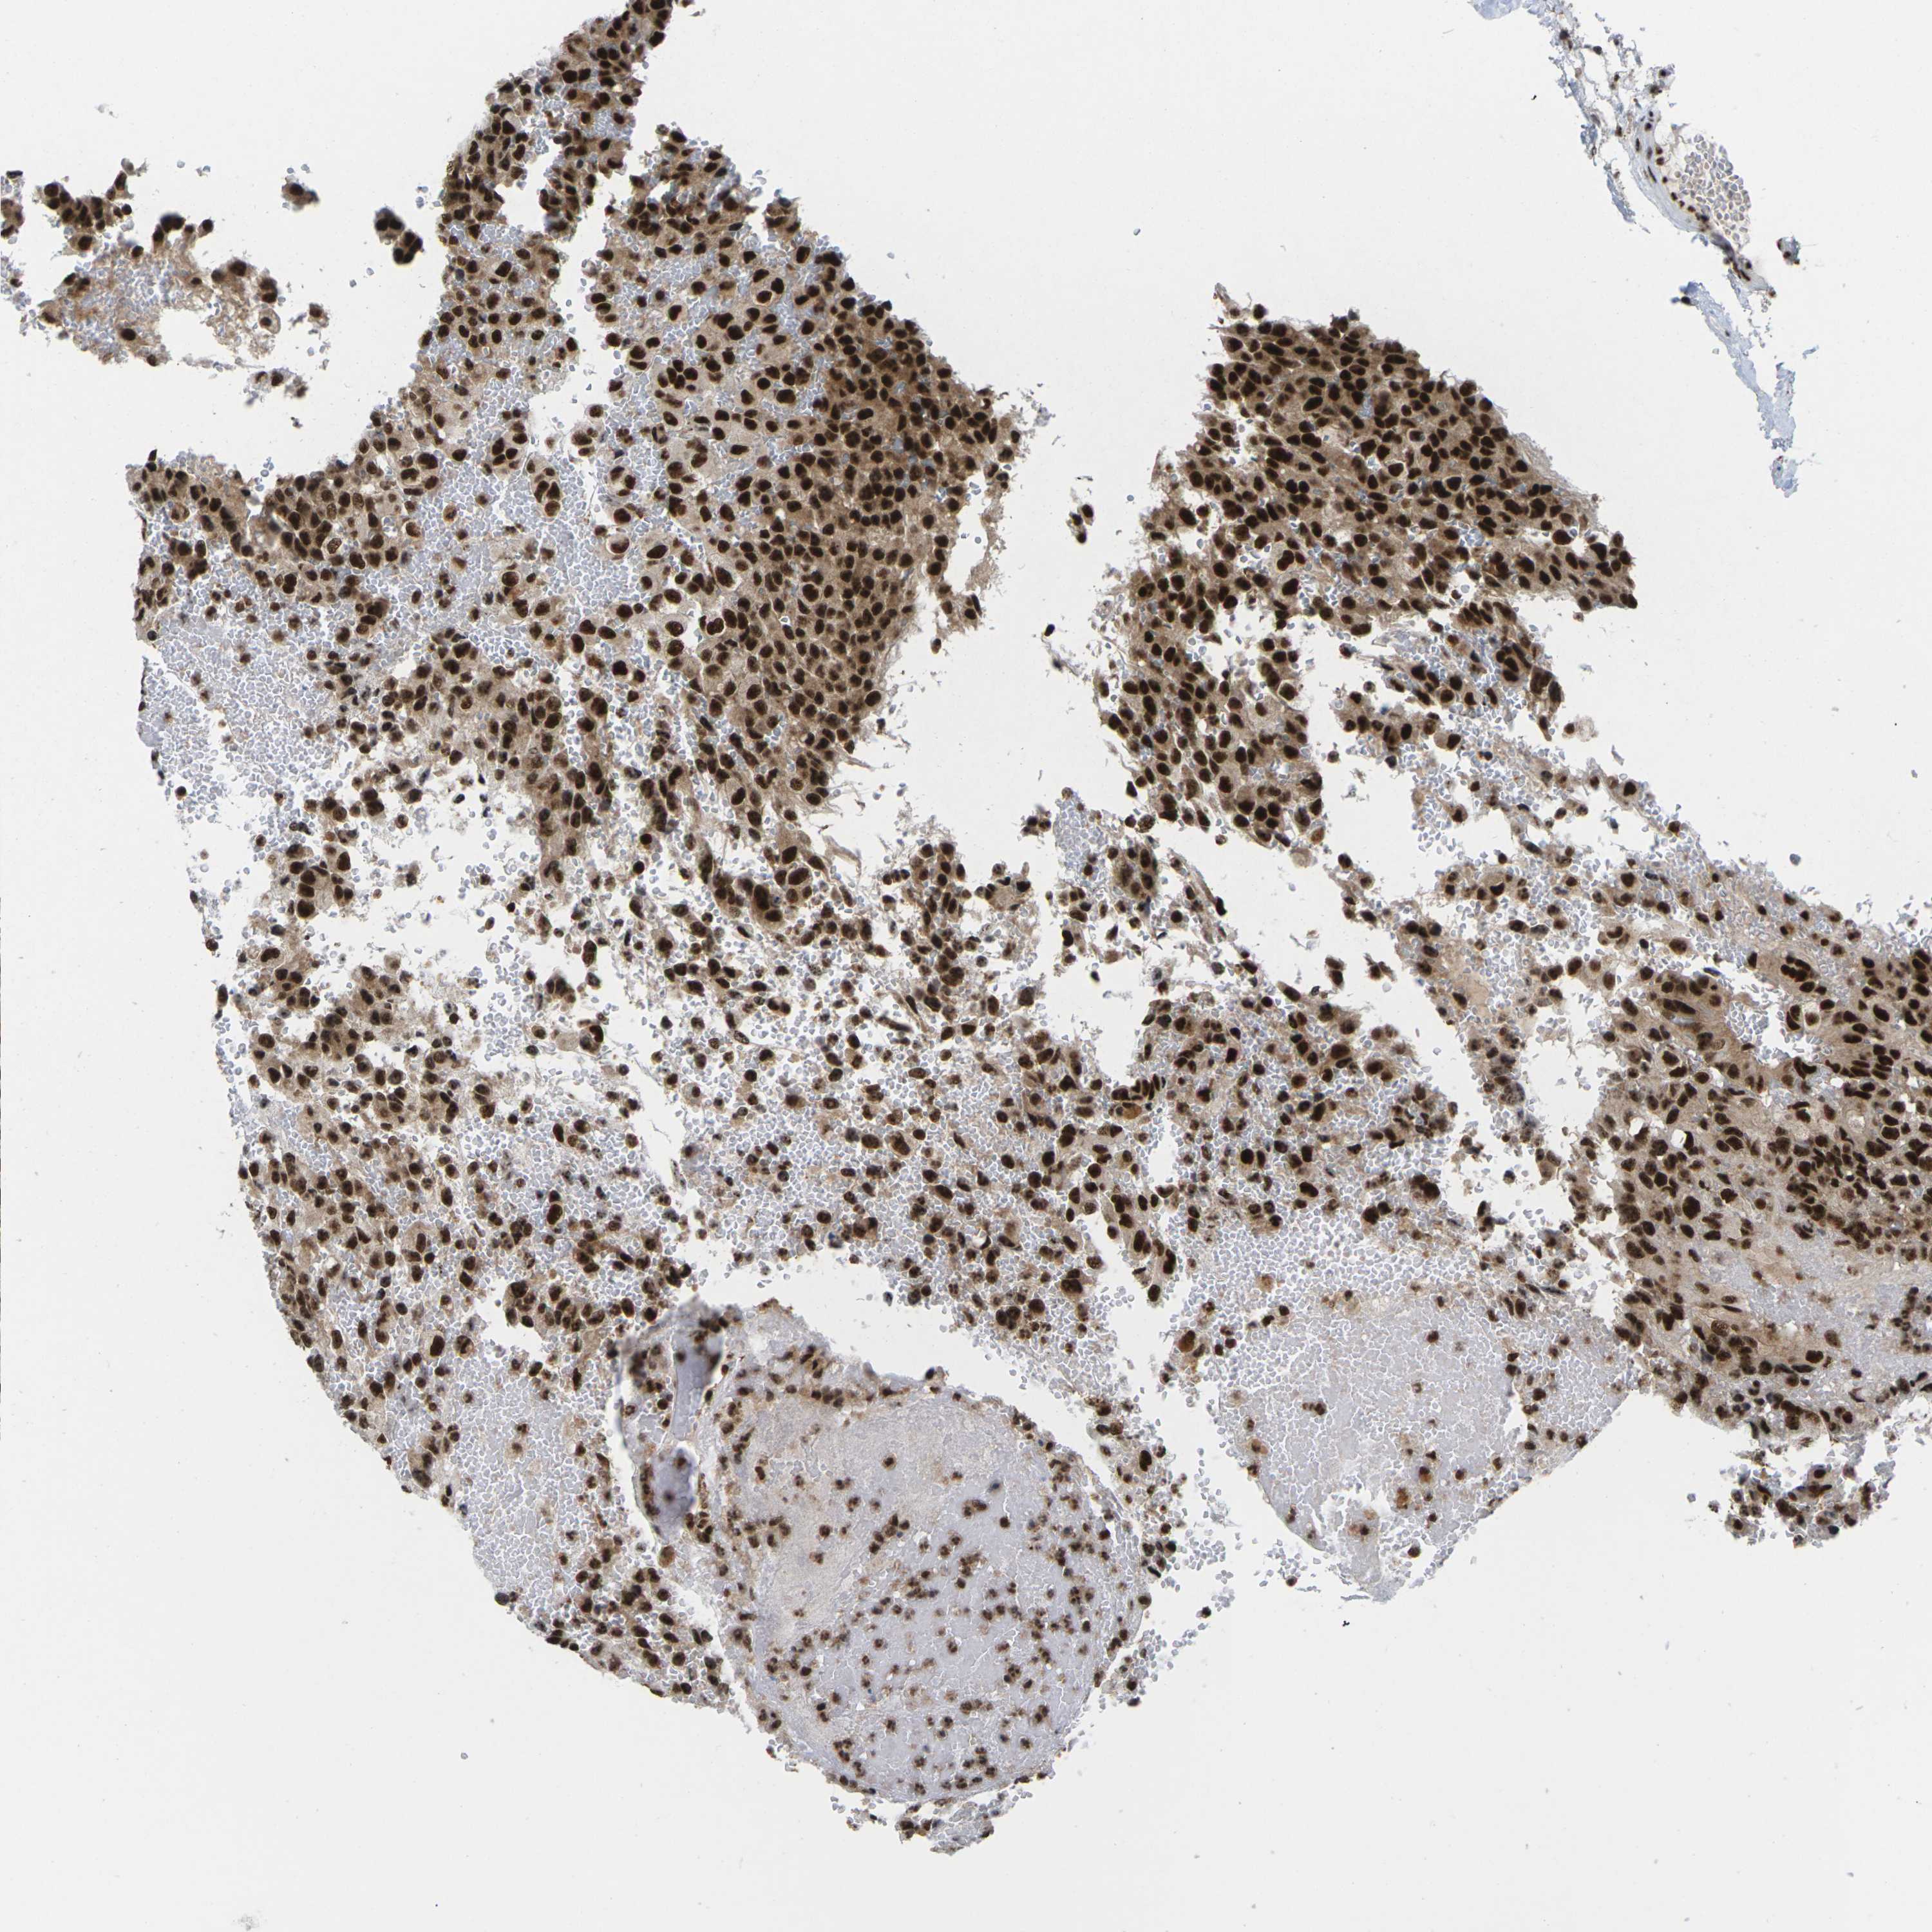

GLIOMA - Protein expressioni

A mouse-over function shows sample information and annotation data. Click on an image to view it in a full screen mode. Samples can be filtered based on level of antibody staining by selecting one or several of the following categories: high, medium, low and not detected. The assay and annotation is described here.

Note that samples used for immunohistochemistry by the Human Protein Atlas do not correspond to samples in the TCGA dataset.

Antibody stainingi

Antibody staining in the annotated cell types in the current human tissue is reported as not detected, low, medium, or high, based on conventional immunohistochemistry profiling in selected tissues. This score is based on the combination of the staining intensity and fraction of stained cells.

Each image is clickable and will lead to virtual microscopy that enables deeper exploration of all samples and also displays staining intensity scores, fraction scores and subcellular localization as well as patient and tissue information for each sample.

Antibody HPA043036

Antibody HPA047754

Antibody CAB015425

Staining

High

Medium

Low

Not detected

Intensity

Strong

Moderate

Weak

Negative

Quantity

>75%

75%-25%

<25%

None

Location

Nuclear

Cytoplasmic/membranous

Cytoplasmic/membranous,nuclear

Glioma, malignant, High grade

Glioma, malignant, Low grade

Glioma, malignant, NOS